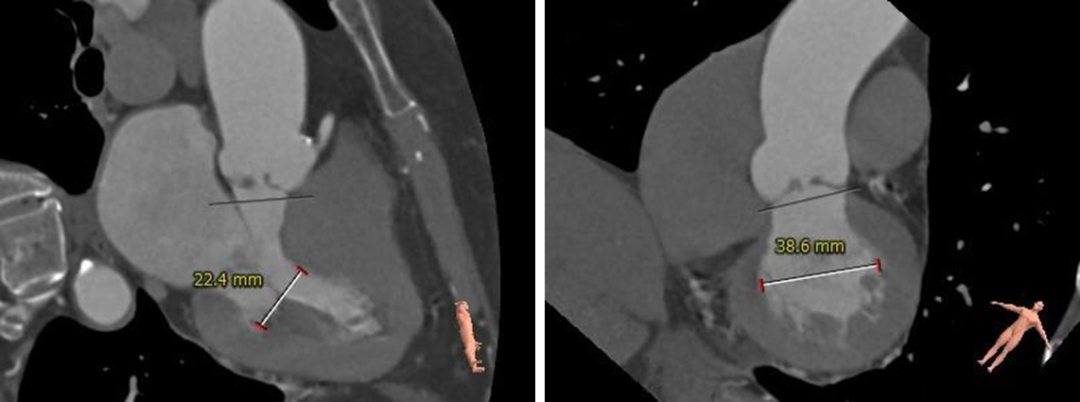

根部测量

三叶式瓣,瓣叶增厚黏连,无钙化

左室测量

左室心肌肥厚